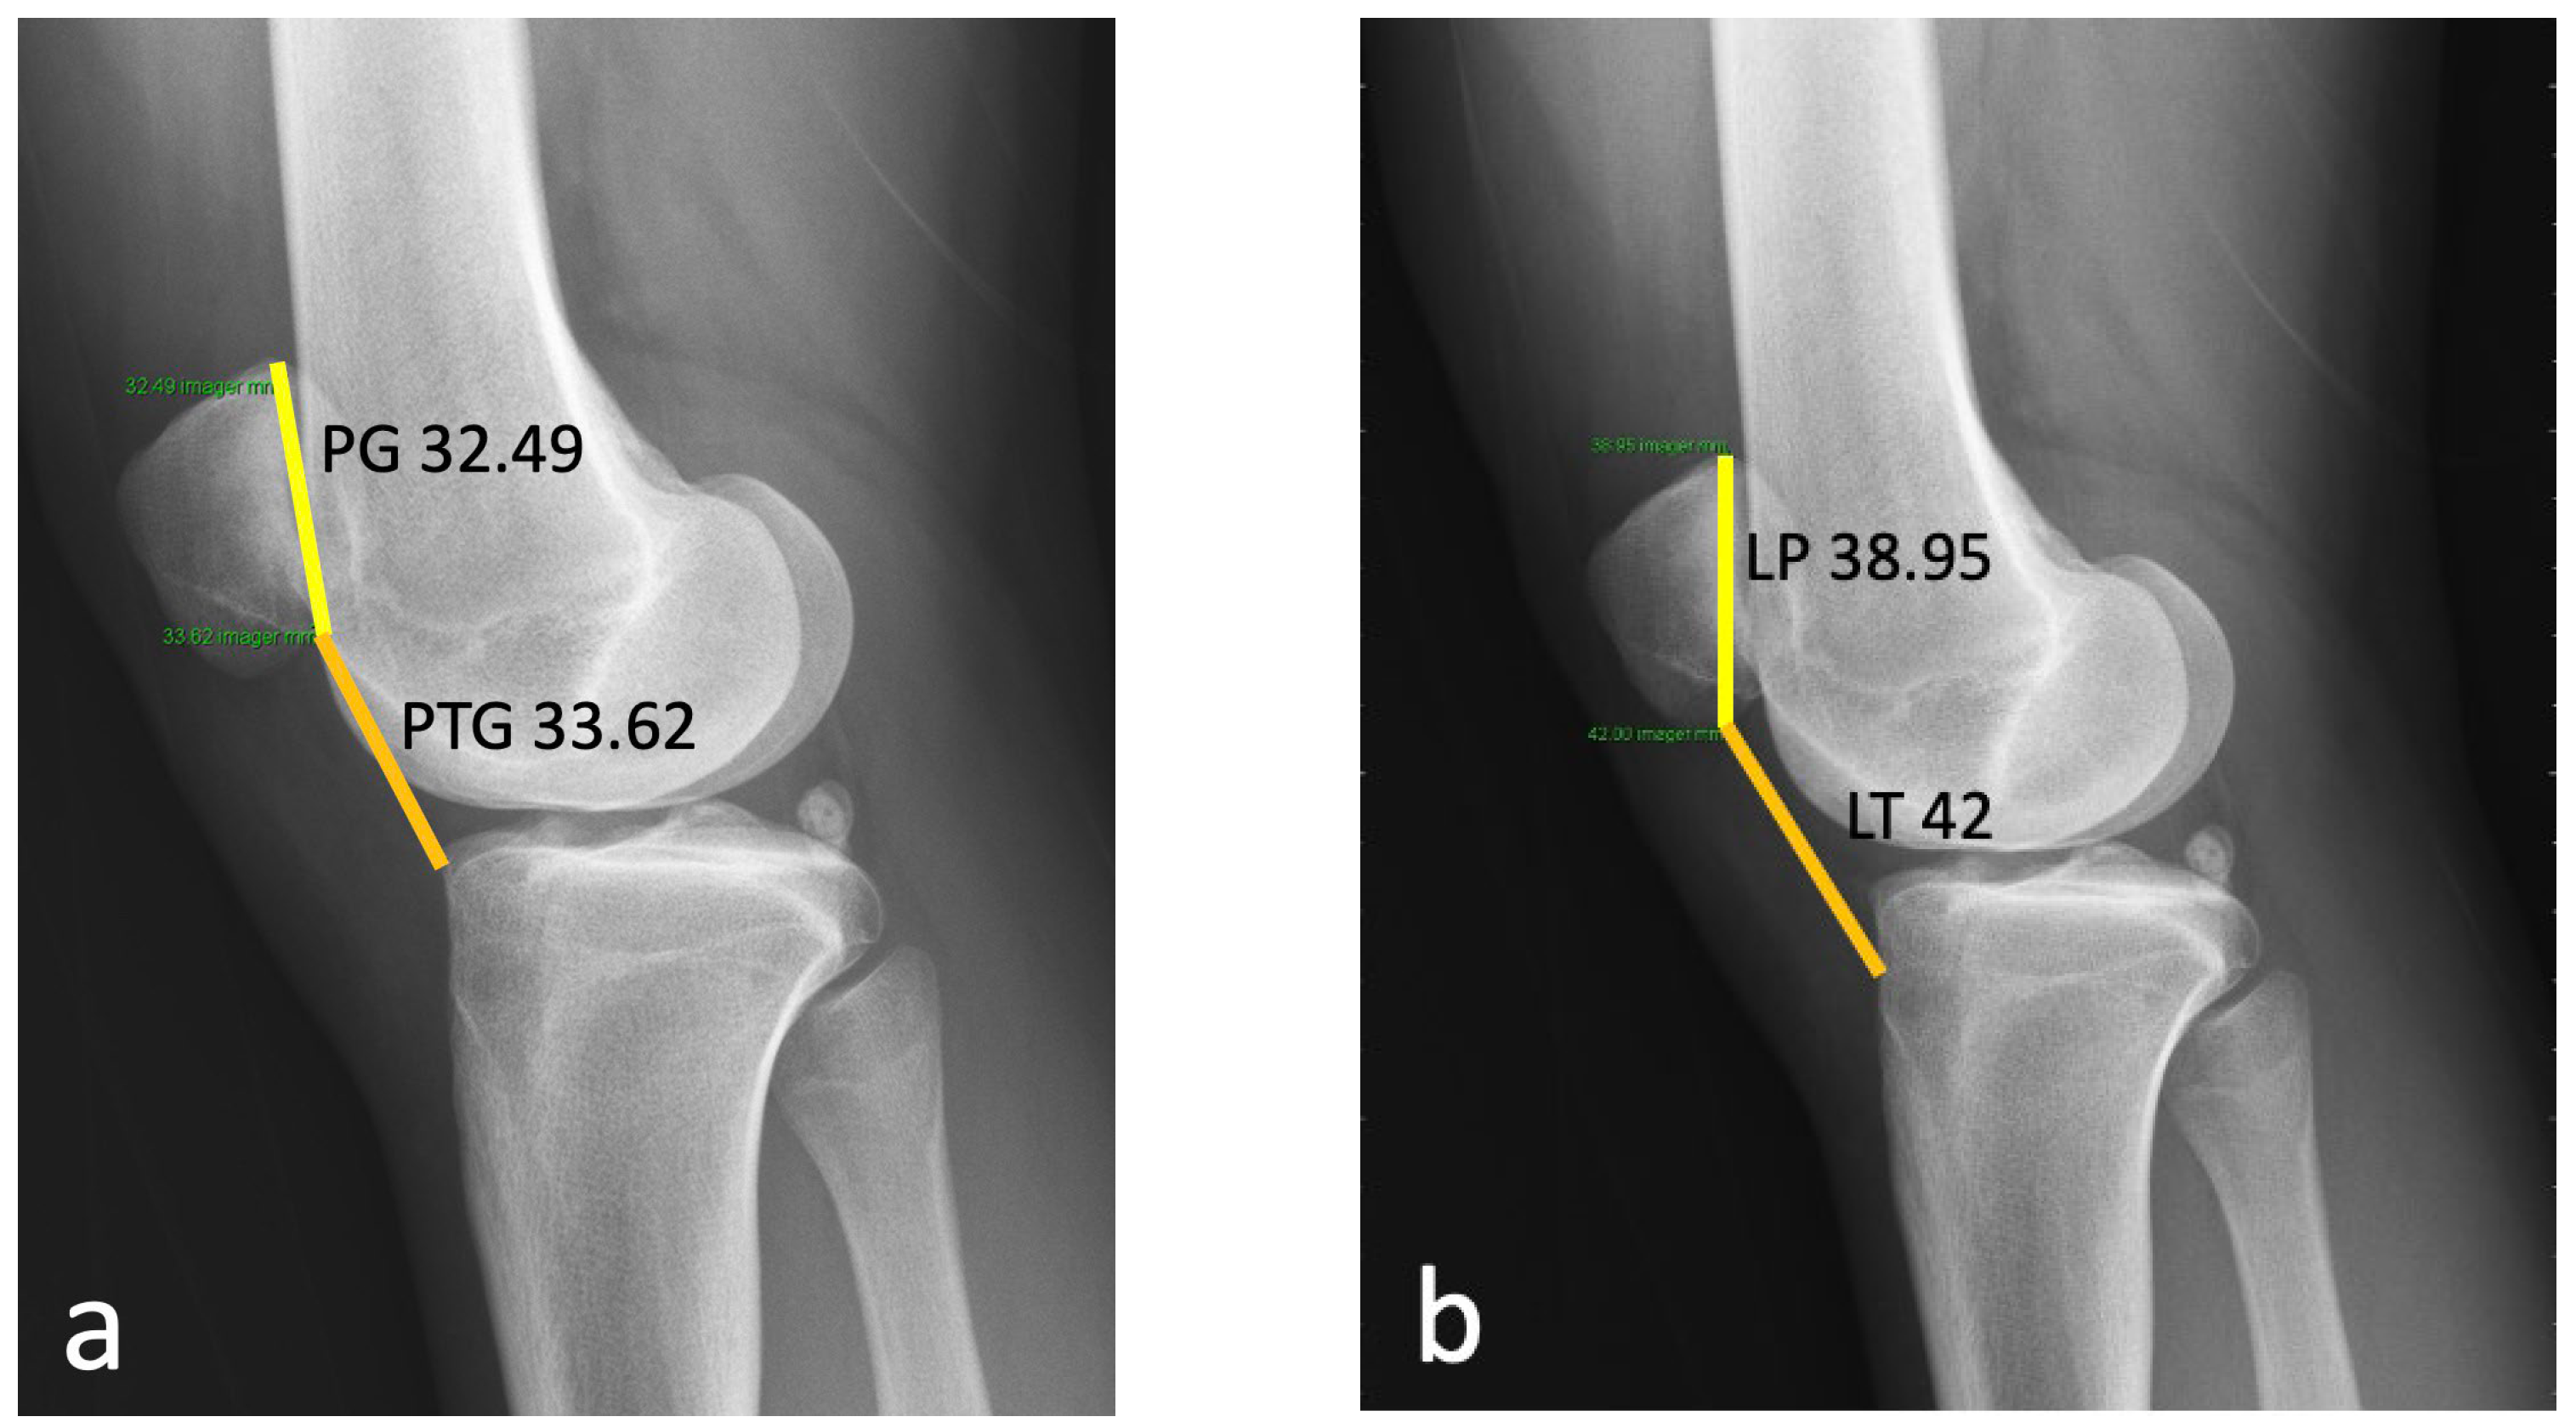

2.1. Case